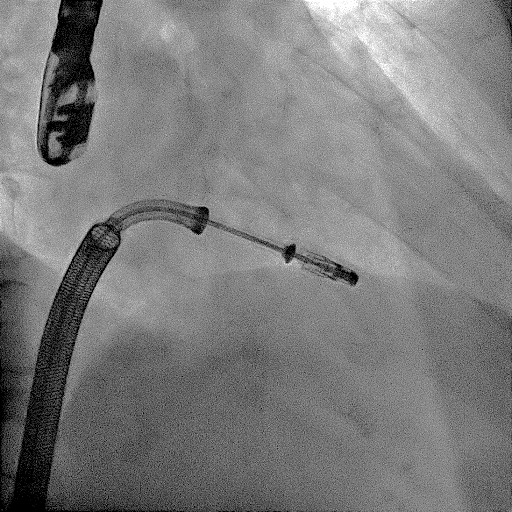

DSA视窗下DragonFly二尖瓣瓣膜夹释放

患者在麻醉科团队保驾护航下,器械经股静脉穿刺房间隔,通过输送系统送入左心房,到达二尖瓣瓣膜反流处,在经食道超声心动图及DSA引导下,术者通过反复评估二尖瓣膜脱垂范围、抓捕位置、反流程度之后,进行精准夹合,成功植入DragonFly瓣膜夹1枚。术后超声即刻患者反流降低至轻度,二尖瓣跨瓣平均压差未超过4mmHg,左房压下降,肺静脉逆流减轻,血流动力学改善明显,手术取得圆满成功。